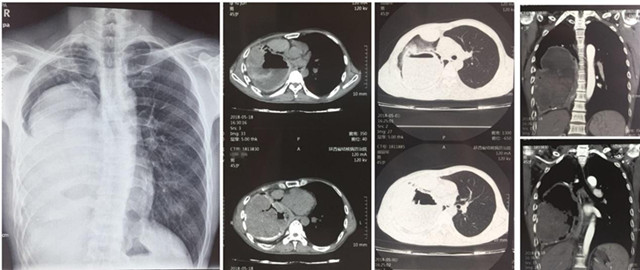

来自渭南澄县的45岁黄某患上了一种奇怪的病,10年前,他无明显诱因出现咳血伴有头晕和乏力,当时由于咳血量小,加之家庭经济条件差并未重视,只要出现该症状都自行购买药物治疗,近5年来咳血频次明显增加,每次咳血量达100ml以上,家人带着他辗转咸阳、西安多家医院,均考虑为肺结核伴脓胸,给予抗痨治疗,但无法有效控制反复出现的咳血症状,眼看黄某身体状况每况愈下,家人心急如焚。5月15日,家人携患者抱着最后一线希望来到陕西省结核病防治院外科,接诊的陈其亮主任医师和李军孝副主任医师对他进行了详细快速的检查,发现患者血压只有90/60mmHg,血色素75g,医生紧急给患者纠正贫血预防休克治疗后,进一步检查发现患者右侧胸腔内可见一罕见的巨大包块,占据80%的胸腔,包块内密度不均匀,右上胸腔仅有的肺组织也呈蜂窝病变结构。让人不解的是,患者既然被我省多家医院诊断为“结核性脓胸”,但从我院诊查后来看,无论是影像形态、生化检查,还是病原病检均无结核感染依据;而且伴随长期咳血的源头是否和占位灶及其滋养血管有关不得而知。目前治疗的唯一手段就是手术,但盲目手术,则是雪上加霜,死亡风险极大。陈其亮科主任及李军孝副主任在科内对患者病情进行详细的讨论和分析后,考虑患者最大的可能是肺源性支气管囊肿并混合感染。由于胸内占位病灶滋养血管丰富,走形错综复杂,压力较大,若不及时控制,患者随时有大咳血至休克死亡的可能。时逢我院承办首届“一带一路”结核病长安论坛之际,陈其亮主任特邀参会嘉宾复旦大学公卫中心胸外科宋言峥主任、山东胸科医院胸外科金锋与影像科候代伦主任为患者会诊,经过论证认为我院外科的针对该病的手术方案(胸膜全肺切除术)指征明确,具有可实施性。

经过精心而充分的准备,陈其亮主任、李军孝科副主任、崔渊博主治医师和麻醉科王君毅医师等按照拟定的手术方案,于5月28日晨8时准时时开始,术中果然出现术前所预料的胸腔创面渗血,肺门粘连及血管畸变等问题,随着手术的推进,患者血压持续偏低(90-60/50-30mmHg),但这些都被我们术前制定的术中紧急应对预案一一化解,经过约4小时50分钟顺利完成胸膜全肺切除,术中共输血3200ml,术后生命体征平稳,术后病理回报印证了术前的诊断。截止目前患者恢复良好,再未出现咳血等呼吸道不适症状,血色素已恢复正常,患者转危为安,家人激动的说:“这么多年的病搞清了,也治愈了”。

据陈其亮主任医师介绍,肺源性支气管囊肿是以支气管组织成分为囊壁、内含黏液或气体的先天性囊肿,曾被称为先天性囊性支气管扩张或先天性支气管源性囊肿。目前病因还不很明确,可能与胚胎发育控制相关,呼吸道上皮与气管支气管树分离,从支气管发育部位移行到其他部位;异常发育出现较早,肺胚芽尚在大气管附近发育时,囊肿位于纵隔或肺门,称为支气管囊肿;而异常发育出现较晚者,异常胚芽易于停留在肺内,囊肿多位于肺内,称为肺囊肿。支气管肺囊肿症状多少及出现的时间,因其所在部位、大小以及有无合并症而异。成人支气管肺囊肿常无症状,多数病例在X线检查或尸解时偶然发现。纵隔内单纯性支气管囊肿以压迫症状为主,如干咳、喘鸣和不同程度的呼吸困难。压迫食管引起吞咽困难和喂养困难。阻塞气道呈活瓣可形成张力性囊肿压迫气管和心脏引起移位,出现明显的气急、发绀。先天性肺囊肿与支气管交通,常继发感染,出现咳嗽、咳痰或咯血,发热,甚至咳大量脓痰,与肺脓肿、支气管扩张相似。少数病人可有囊肿内大量出血,破溃至胸腔,产生自发性气胸或血气胸。体征因囊肿大小不同而异,较大囊肿充满液体,叩诊呈局部实音;较大气性囊肿叩诊可有局部鼓音,听诊时呼吸音减弱或消失。囊肿较小位于肺实质内无继发感染,则可无任何症状和体征。手术是此类疾病的唯一治疗方法,且实施手术的时间越早越好,切忌随意行诊断性囊肿穿刺抽液,以免囊肿内液体漏入胸膜腔难以吸收。手术不受年龄限制,但3岁以内手术较年长儿恢复快,肺扩张好,后遗症少。7岁以上因病程长,反复感染,胸腔内可能有广泛粘连,则手术出血多,恢复也慢。我科收治的这例肺源性支气管囊肿患者,患病时间长,囊肿病灶如此巨大,与胸腔广泛粘连并存在严重钙化实属罕见,经查文献报道成功救治同类的案例的较少,此情况极易误诊。由于该患者病肺存在先天血管及气管畸变,胸腔内反复感染,胸膜滋养血管丰富,行胸膜全肺切除术时,游离病肺及解剖肺门困难,极易出现大血管出血及胸膜创面广泛渗血,控制难度大,死亡率极高。幸运的是该患者病肺多数血管萎缩或闭锁,加之术前做了充分的准备,才使患者顺利康复,并使我们获得了宝贵了经验,拓展了胸科的业务范围。今后,对于胸腔包裹性占位并咳血的患者,一定要怀疑到肺源性支气管囊肿的可能,精准判断才能克病致胜。